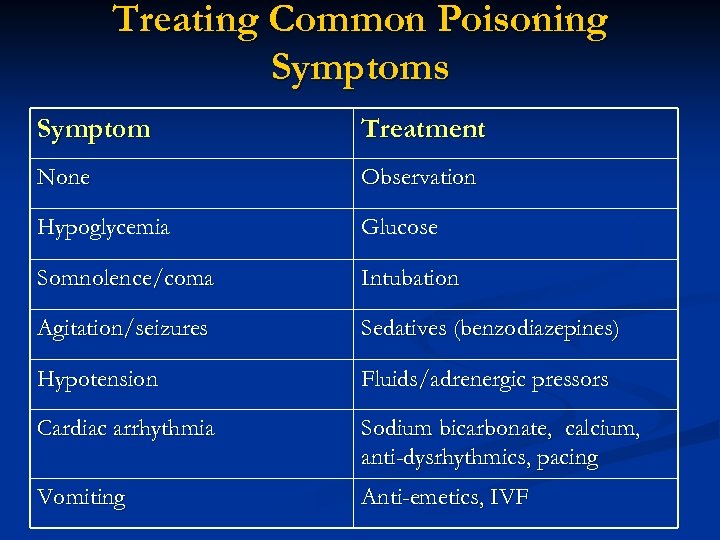

Treating Common Poisoning Symptoms Symptom Treatment None Observation Hypoglycemia Glucose Somnolence/coma Intubation Agitation/seizures Sedatives (benzodiazepines) Hypotension Fluids/adrenergic pressors Cardiac arrhythmia Sodium bicarbonate, calcium, anti-dysrhythmics, pacing Vomiting Anti-emetics, IVF

Treating Common Poisoning Symptoms Symptom Treatment None Observation Hypoglycemia Glucose Somnolence/coma Intubation Agitation/seizures Sedatives (benzodiazepines) Hypotension Fluids/adrenergic pressors Cardiac arrhythmia Sodium bicarbonate, calcium, anti-dysrhythmics, pacing Vomiting Anti-emetics, IVF